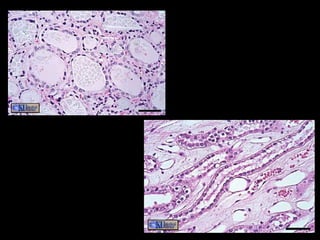

Glands

• One or more cells that make and secrete a product.

• Secretion = protein in aqueous solution: hormones,

acids, oils.

• Endocrine glands

– No duct, release secretion into blood vessels

– Often hormones

– Thyroid, adrenal and pituitary glands

• Exocrine glands

– Contain ducts, empty onto epithelial surface

– Sweat, Oil glands, Salivary glands, Mammary glands.

Shapes of Exocrine glands

Branching

 Simple – single, unbranched duct

 Compound – branched.

Shape: tubular or alveolar

 Tubular – shaped like a tube

 Alveolar – shaped like flasks or sacs

 Tubuloalveolar – has both tubes and sacs in

gland

Glands • One ormore cells that make and secrete a product. • Secretion = protein in aqueous solution: hormones, acids, oils. • Endocrine glands – No duct, release secretion into blood vessels – Often hormones – Thyroid, adrenal and pituitary glands • Exocrine glands – Contain ducts, empty onto epithelial surface – Sweat, Oil glands, Salivary glands, Mammary glands.

Shapes of Exocrineglands Branching  Simple – single, unbranched duct  Compound – branched. Shape: tubular or alveolar  Tubular – shaped like a tube  Alveolar – shaped like flasks or sacs  Tubuloalveolar – has both tubes and sacs in gland